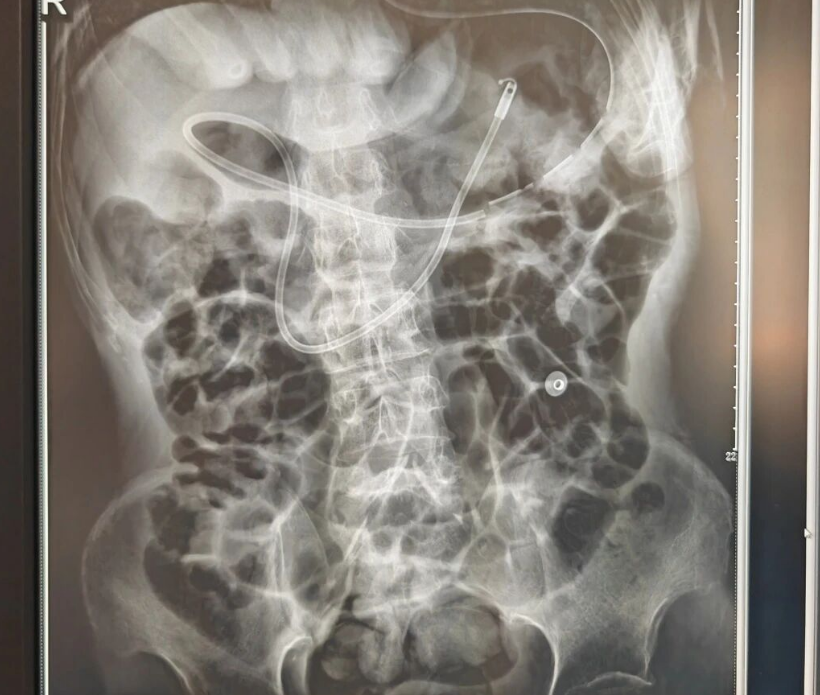

9月10日,在胃镜室主治医师的操作下,团队顺利为患者置入空肠营养管。整台操作流程顺畅、定位准确,术中患者生命体征平稳,未出现任何并发症。术后腹部平片显示导管位置良好,当日即开始肠内营养输注,成功解决营养支持难题。

术后腹部平片显示导管位置良好